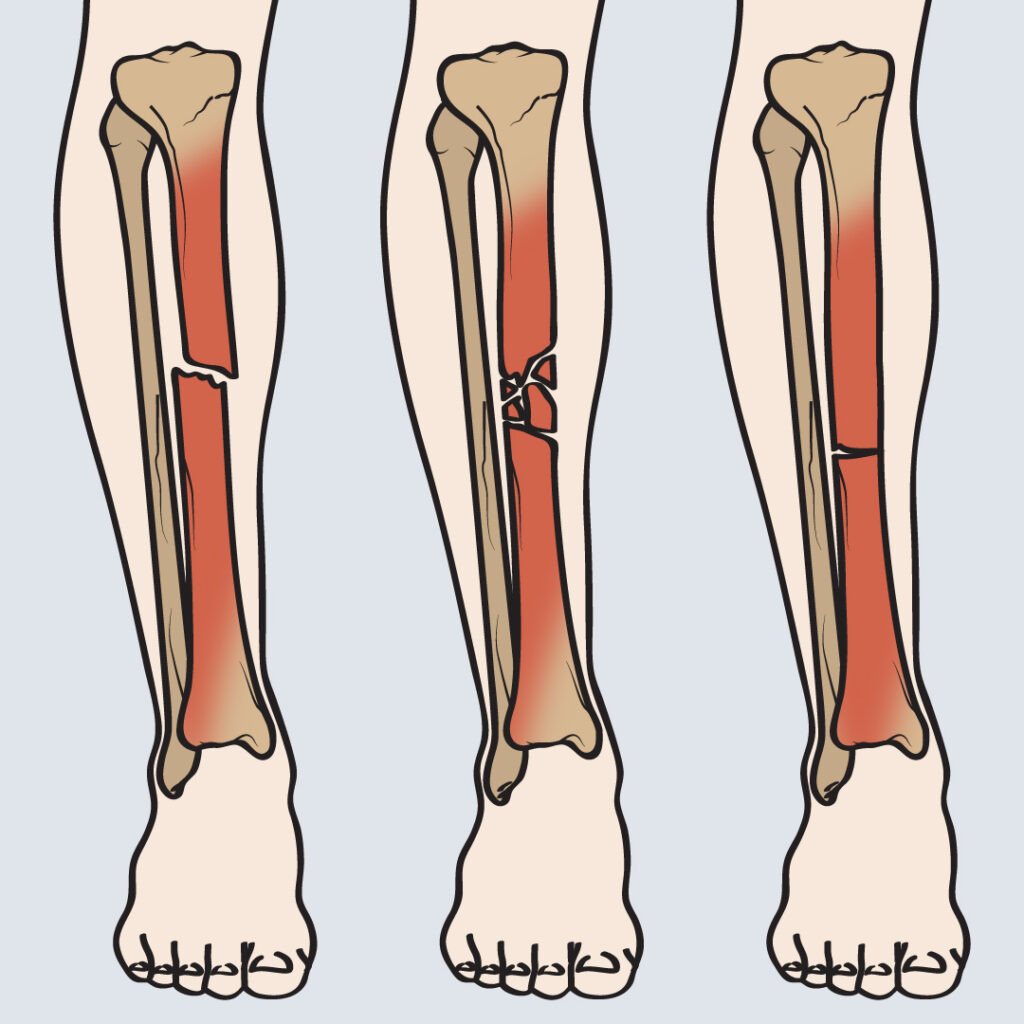

Fraktur Tibia

Tibia atau tulang kering merupakan tulang panjang tersering yang mengalami patah (fraktur). Kondisi ini terjadi pada sekitar 4% populasi lanjut usia.